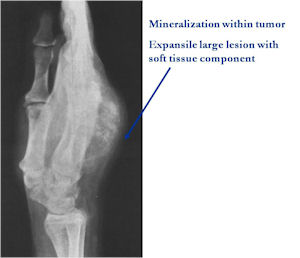

- Geographic, circumscribed lesion usually around 5cm in size.

- There may be expansion of bone, cortical thinning and cortical breakthrough. A soft tissue mass may accompany this lesion but the soft tissue component is usually contained by the periosteum.

- The periosteum remains intact around the soft tissue component. Might need a CT scan to detect the subtle calcification (Egg Shell Rim of Calcification) associated with an intact periosteal reaction

- The lesion may be entirely radiolucent but usually shows some degree of mineralization. Mineralization may appear stippled like cartilage but do not see chondroid pathologically. Mineralization is sometimes better detected on a CT scan rather than an x-ray.